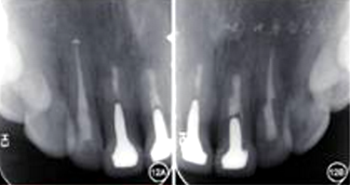

見圖12,圖13。臨床檢查叩診正常,不松動,牙齦色澤正常,切口位置可見隱約瘢痕。根尖X線片顯示根尖無明顯病變。

圖12 術(shù)后2年復(fù)查患者根尖X線片 A:根尖無明顯病變;B:根尖無明顯病變